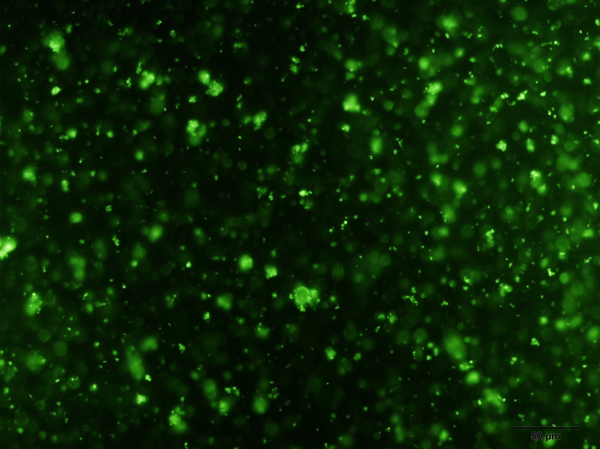

GPIV POSITIVE PLATELETS